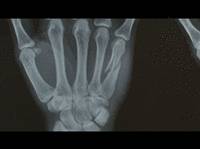

21 year old Kosmowski, who finished the 2008 PWA freestyle season in 19th position, has fractured a bone in his left hand during winter training in Cape Town.

"I went out on my 4.5m, it was all good. But then the wind picked up and it got really gusty. I was going for a no-handed flaka; everything was ok, I took off, threw the sail, then this massive gust came and the sail just snapped down into the water. I fell with all the pressure on my hand and broke the bone."